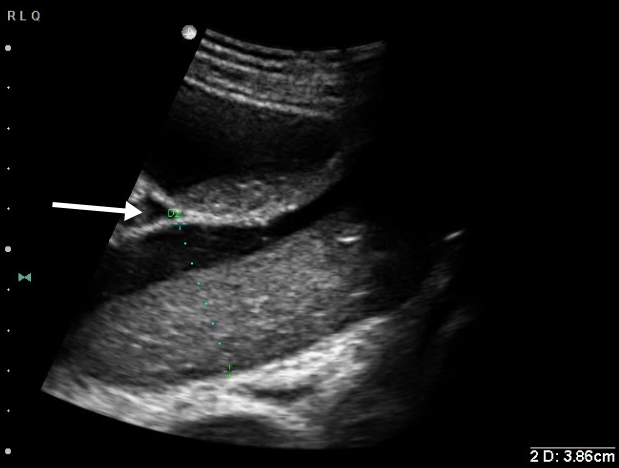

- The diagnosis of SBO is additive. Pathologic findings include dilation of small bowel > 2.5 cm (see Fig. 1), abnormal (“to and fro”) peristalsis (see Video 2), bowel wall thickening, and the presence of extraluminal free fluid between loops of bowel (see Video 3).

- Figure 1. Significantly dilated loop of small bowel. Also note free fluid interposed between loops of bowel (white arrow).